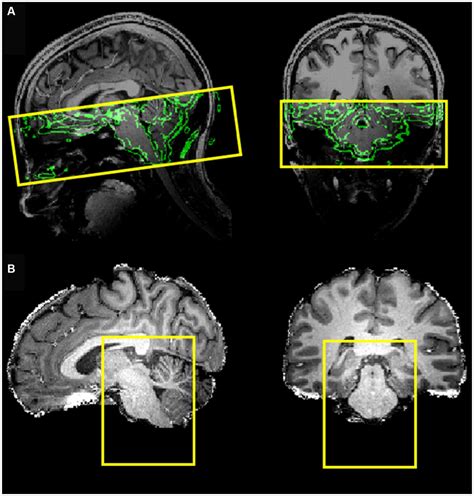

Brainstem representation

The Tractus Solitarius Nucleus is a long, vertical column of grey matter embedded in the medulla oblongata. It is uniquely organized into various sub-nuclei, each specialized to handle specific sensory inputs. These inputs arrive primarily through cranial nerves VII (facial), IX (glossopharyngeal), and X (vagus).